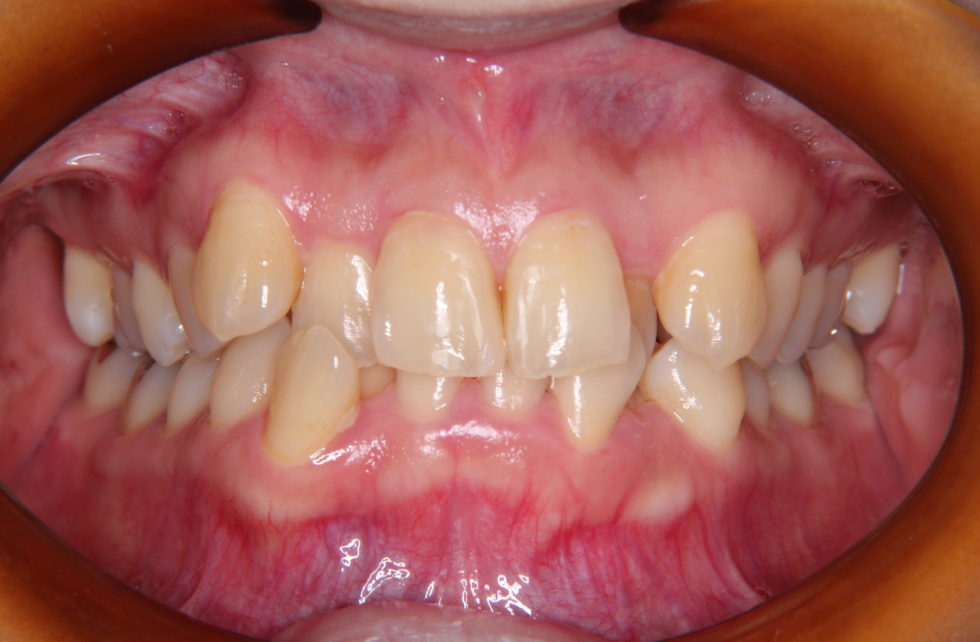

初診時年齢36歳女性。上下顎前歯の叢生を主訴として来院された。

上下の犬歯が唇側転位となっていた。上顎小臼歯、下顎歯患者さんの希望もあり犬歯を抜歯していただき上顎舌側、下顎唇側マルチブラケット装置を使用して動的治療を行った。   動的治療期間は1年4か月間